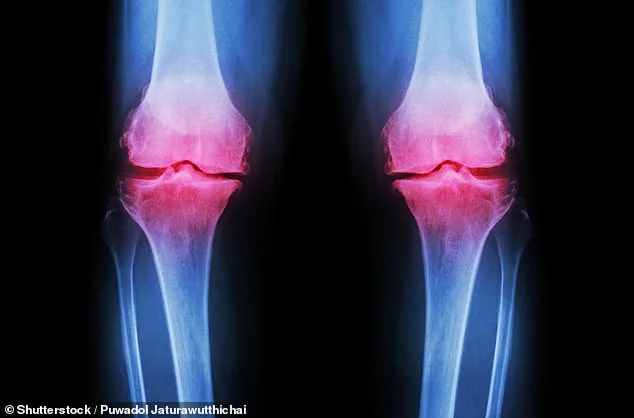

Scientists at Columbia University have unveiled a groundbreaking approach to treating osteoarthritis, a condition that affects over 32 million Americans and causes severe pain, stiffness, and mobility loss. The research involves creating a lab-grown knee using a 3D-printed scaffold made from biodegradable material. This scaffold is seeded with bone and cartilage cells, which regenerate into natural joint tissues over about a year as the scaffold dissolves. The resulting living knee could be transplanted into patients, offering a permanent solution for those suffering from knee osteoarthritis, which affects 14 million Americans and is a leading cause of disability in the United States. Current treatments, such as pain management, injections, or joint replacement surgery, are either temporary or invasive. This new method aims to restore function by integrating the lab-grown joint with the patient's blood vessels, allowing it to function like a natural knee.

Osteoarthritis, the most common form of arthritis, has seen a staggering surge in prevalence over the past three decades. According to global health data, the number of patients has increased by 132% since 1990, with projections suggesting this trend will continue as populations age and obesity rates climb. Doctors warn that while aging and weight gain are major contributors, the condition disproportionately affects women and individuals from lower socioeconomic backgrounds. These disparities are linked to factors such as limited access to preventive care, higher rates of manual labor jobs that strain joints, and a greater likelihood of developing comorbid conditions like diabetes or hypertension. As the number of people living with osteoarthritis grows, so does the demand for innovative treatments. Traditional approaches—such as physical therapy, painkillers, and joint replacements—are increasingly strained by the scale of the crisis.